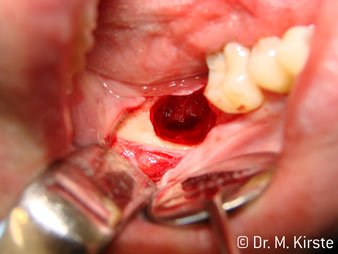

The 45° angle of the handpiece has been specially selected for its wide range of advantages. Colleagues who work in surgery, and for whom this handpiece was primarily developed, will soon appreciate the ability to work efficiently in very restricted spaces. In wisdom tooth extractions in particular (fig. 2) there is no need for large-scale spreading of the soft tissues in the cheek region (fig. 3). The design of the handpiece head combined with turning the head slightly during preparation allows work to be carried out quickly and safely in the retromolar region.

The professional design of the bearings inside the handpiece head guarantees quiet running of the bur; this makes for an impressively atraumatic cut in the separation of tooth and root (fig. 4-9).

Fig. 2

Fig. 3